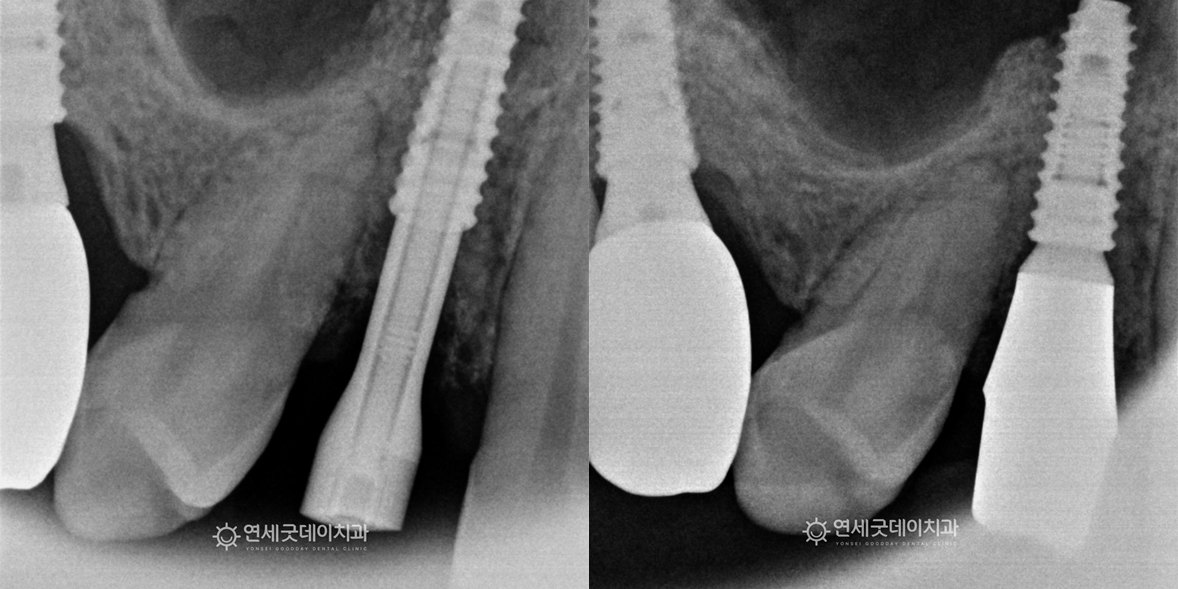

잇몸이식 및 임플란트 재수술 치료전후 - 20대 남성

먼 제주에서 임플란트 재수술을 주소로 내원해주신 20대 남성 환자분이십니다.

▲ 치료 전 (촬영시기 : 2024년 11월)

환자분은 7년 전 타병원에서 뼈이식과 임플란트를 했으나

앞서 2024년 11월경 타원 임플란트를 제거하고

약 3개월 뒤, 잘 보강된 잇몸뼈에 픽스쳐를 심었으며

임플란트 재수술과 잇몸이식으로 잇몸이 정상 형태로 완화되었으며